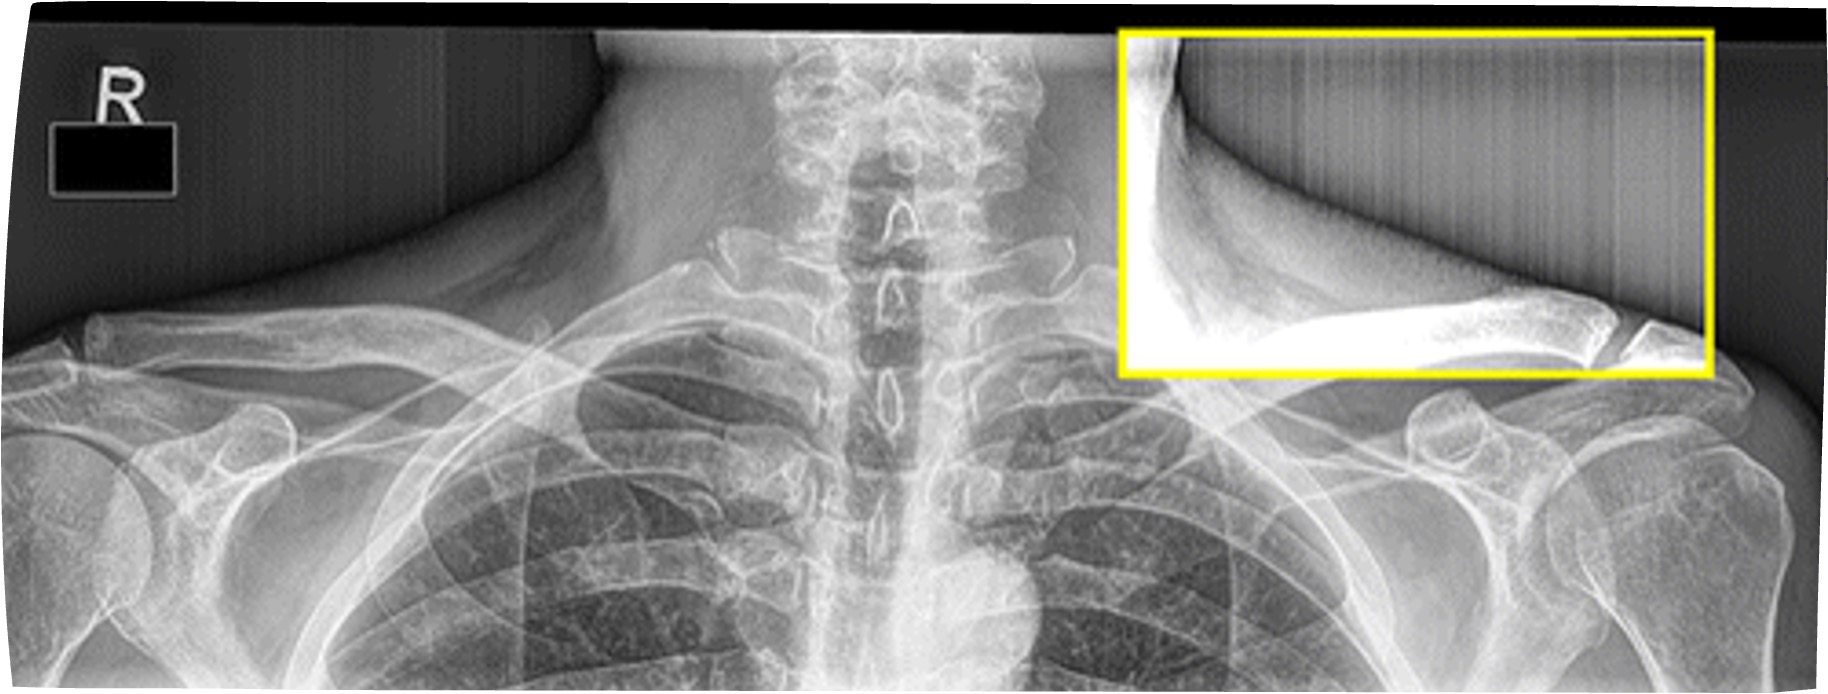

* Histogram analysis error- need to collimate

Correct Collimation is crucial - lowest exposure regions of a histogram can represent collimated borders

Asymmetrical collimation causes problems in CR b/c CR is processed looking for 2 or 4 borders